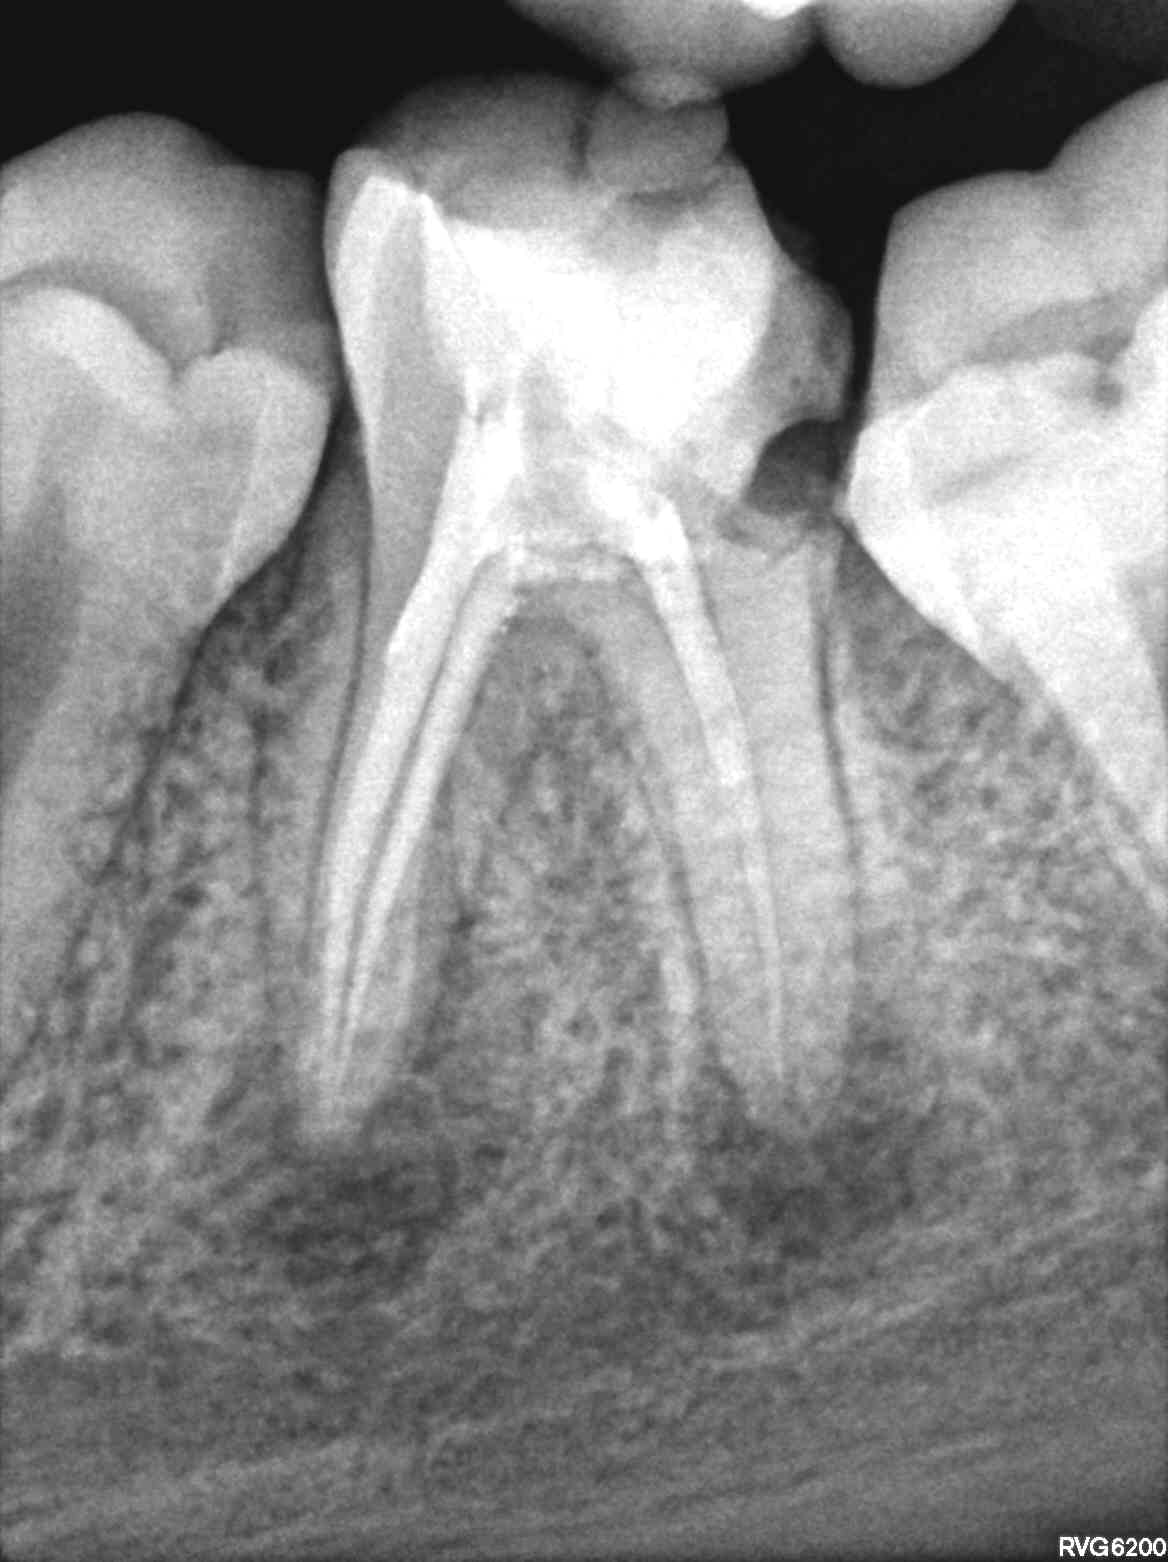

👨⚕️ 𝐍𝐨𝐭𝐫𝐞 𝐜𝐨𝐫𝐫𝐞𝐬𝐩𝐨𝐧𝐝𝐚𝐧𝐭 𝐧𝐨𝐮𝐬 𝐝𝐞𝐦𝐚𝐧𝐝𝐞 𝐬𝐢 « 𝐥’𝐞𝐧𝐝𝐨 𝐞𝐬𝐭 𝐫𝐞́𝐚𝐥𝐢𝐬𝐚𝐛𝐥𝐞 ».

Techniquement, oui.

Mais est-elle pour autant indiquée ❓